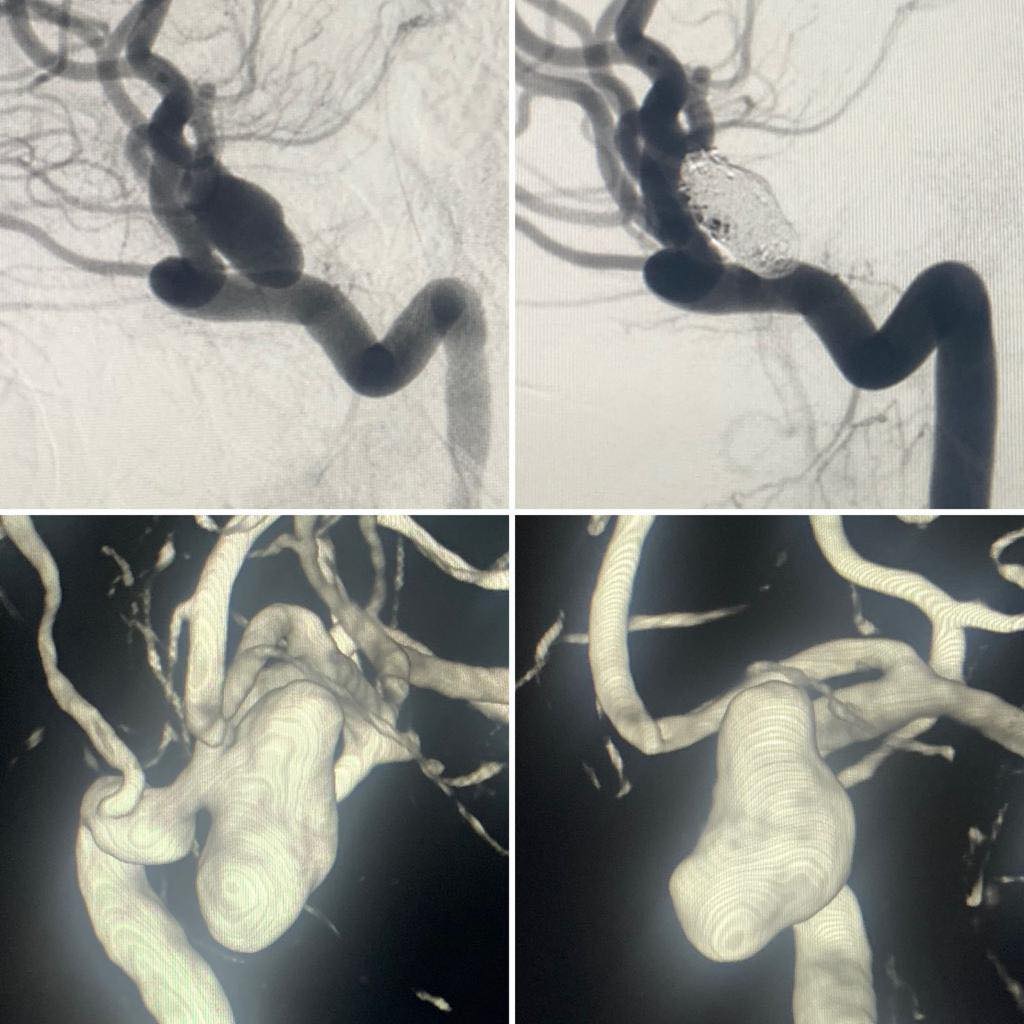

Снимки и иллюстрации микроаневризм сосудов головного мозга